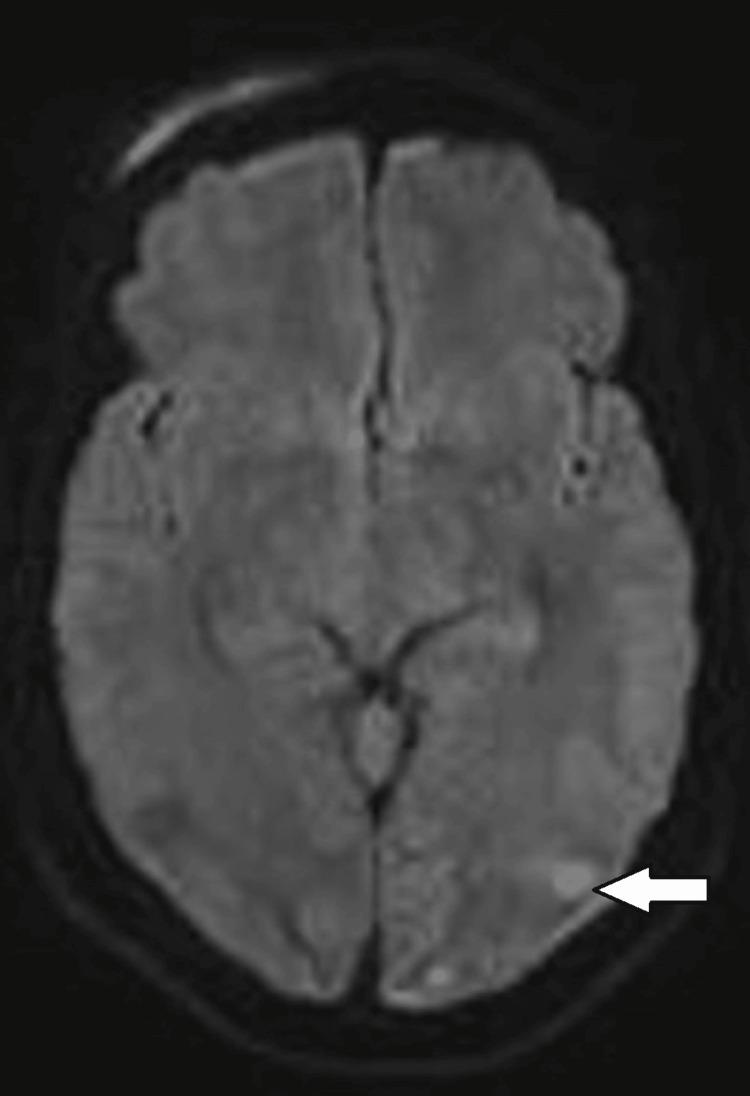

The defining characteristic of posterior reversible encephalopathy syndrome (PRES) is a reversible, predominantly vasogenic edema of the white matter, particularly affecting the parenchyma supplied by the posterior circulation. PRES is most commonly associated with hypertension. We present a case series of seven normotensive patients diagnosed with cancer who had posterior reversible encephalopathy syndrome.

The median age of patients in this study was 48 years. No patient exhibited significantly elevated blood pressure during their inpatient stay. Altered consciousness with seizures was the primary initial manifestation in most patients, followed by headache. The predominant observation on the MRI was T2 flair hyperintensity in the posterior circulation. All subjects attained nearly full neurological recovery by 28 days, regardless of steroid therapy. The 90-day all-cause mortality rate was 14% (one out of seven patients). There were no fatalities attributable to PRES.

本研究中患者的中位年龄为48岁。所有患者在住院期间血压均无显著升高。意识改变伴癫痫发作是大多数患者最初的主要表现,其次是头痛。MRI的主要表现是后循环区域T2加权像高信号。所有受试者在28天时几乎都实现了神经功能的完全恢复,无论是否接受类固醇治疗。90天全因死亡率为14%(七名患者中的一名)。没有因PRES导致的死亡病例。